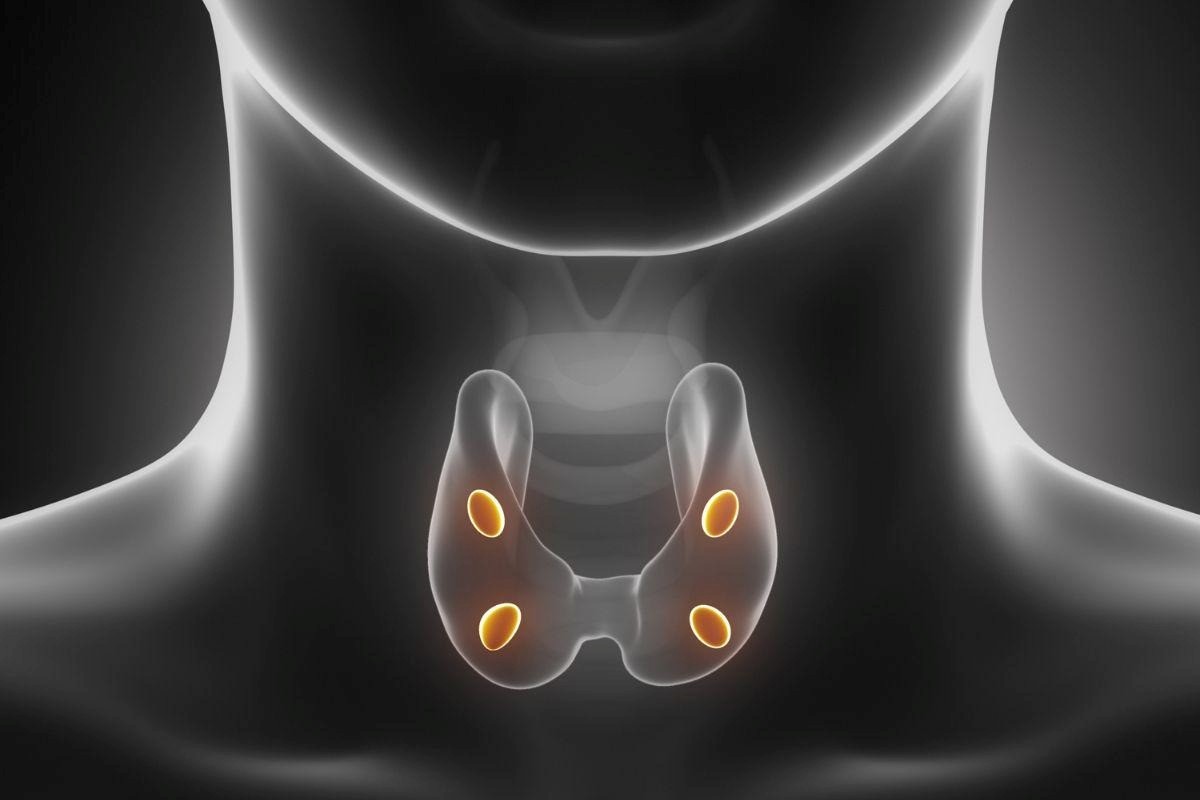

Ambas envolvem o funcionamento das glândulas paratireoides, presentes em número de quatro e próximas à tireoide, que são responsáveis pela produção do paratormônio (PTH), hormônio essencial para o equilíbrio do cálcio, do fósforo e da saúde óssea.

Qual é a função das paratireoides no organismo?

As paratireoides são pequenas glândulas localizadas atrás da tireoide e têm como principal função regular os níveis de cálcio no sangue por meio da produção do PTH.